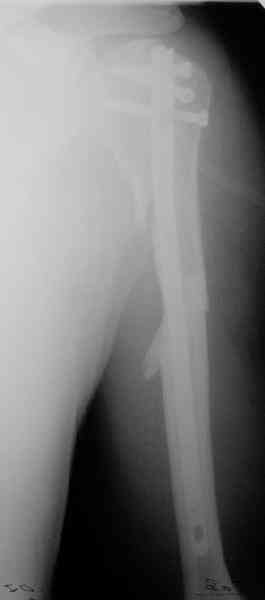

Попытка закрыто изменить положение не удалась. Передним доступом сделали открытую репозицию, гленоид без особенностей. Временно фиксировали спицами и остроконечным костедержателем. Фиксировали гвоздем T2 PHN (Stryker). Для профилактики вывихов после введения проксимальных винтов ротировали дистальный отдел кнаружи на 30

градусов как аналог остеотомии по Weber. Снимки в приложении. Комментарии и критика привествуются.

Attempt of closed reduction failed. Open reduction via anterior approach. The head was temporarily fixed by wires and sharp clamps. Fixation by a nail - T2 PHN (Stryker). The distal fragment has been rotated 30 degrees externally after proximal locking for dislocation prevention as "virtual" Weber osteotomy. Images attached.

Comments/critics are welcome.